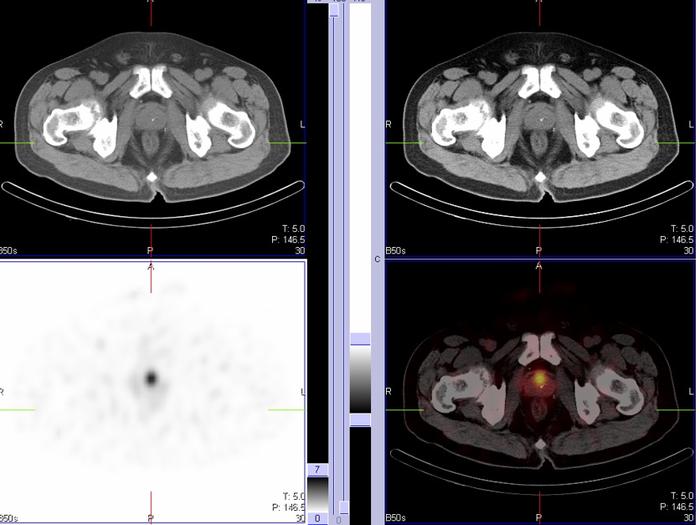

2.PSMA-PET/CT的应用及优势

1) PSMA-PET/CT的应用

PSMA的细胞外活性部分(叶酸水解酶Ⅰ)可被 11 C18 F89 Zr64 Cu86 Y68 Ga等多种放射性核素标记 , 而68 Ga18 F是靶向PSMA的优良显像剂,68 Ga-PSMA18 F-PSMA具有良好的生物学分布及对PCa细胞亲和力高,进行PET/CT显像时,能够得到反映PCa病灶在体内分布的影像。

PSMA-PET/CT具有更高的灵敏度、特异度及转移灶的早期检出率,可对PCa进行精准分期,在PSA 水平较低时也能够有效发现转移病灶